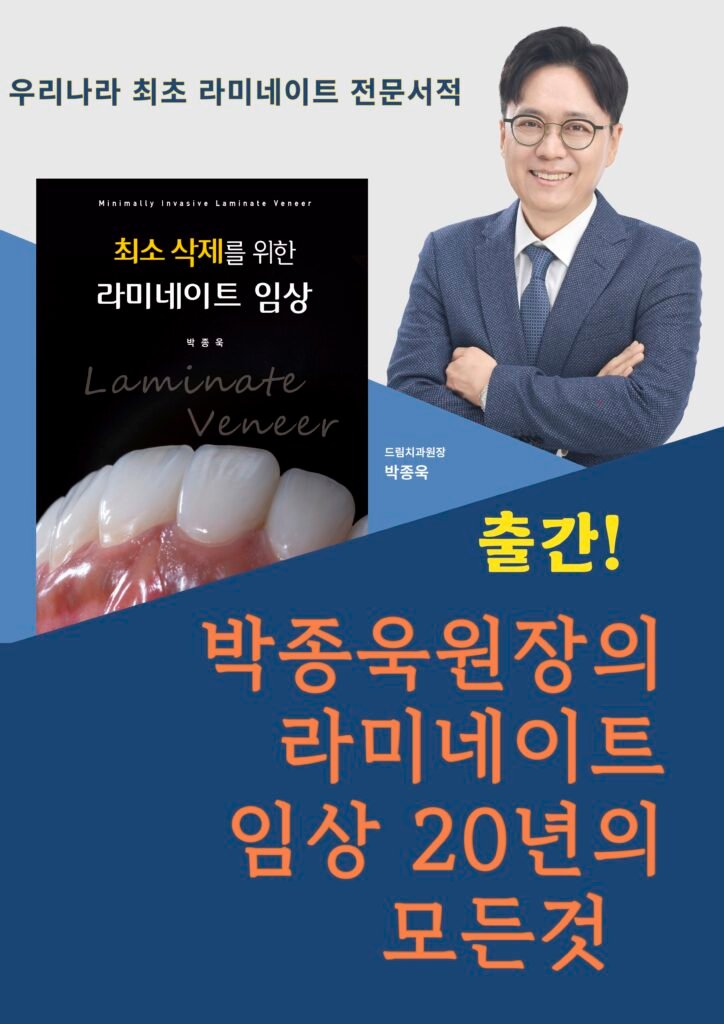

Over 27 years of clinical experience by Dr. Jonguk Park at Dream Dental Clinic in Apgujeong.

Dream Dental Clinic(드림치과)은 2006년부터 압구정동에서

**자연스러운 라미네이트(Laminate Veneer)**를 전문으로 해왔습니다.

박종욱 원장은 1998년부터 27년 넘게 임상에 집중하며

수많은 라미네이트 강의와 교과서를 통해

한국 심미치과의 기준을 만들어 왔습니다.

Dr. Jonguk Park은 27년의 임상 경험을 바탕으로

치아의 생리적 구조를 최대한 보존하며,

자연스러운 투명감과 깊이감이 살아 있는 라미네이트를 추구합니다.

Dream Dental Clinic은 빠름보다 정확함을,

양보다 정성을 중요하게 생각합니다.